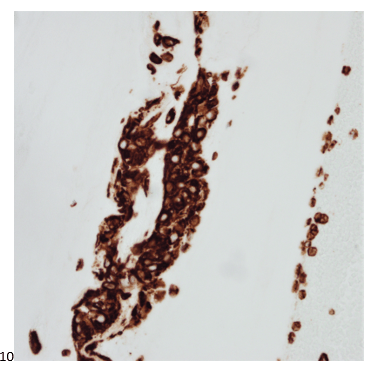

P.S. Sometimes diving and cytology overlap under the microscope, too!